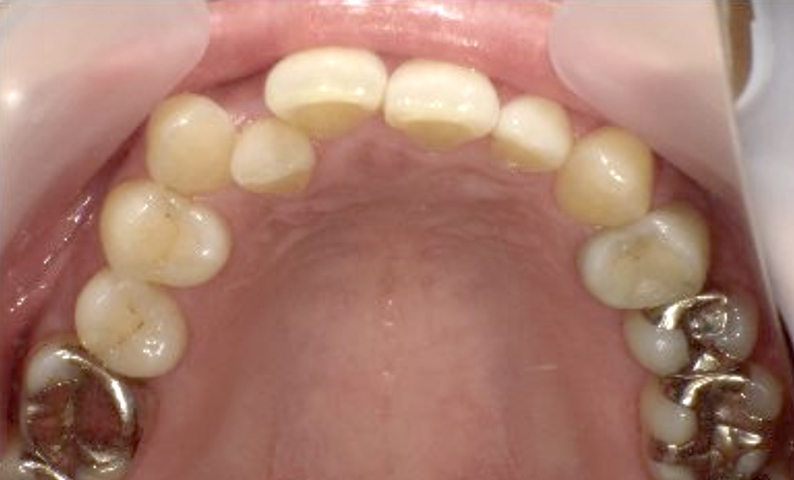

症例_002 上顎だけの部分矯正

治療期間:7ヶ月金額:30万円+税女性前歯のガタガタ上の前歯だけ

| Before | After |

|---|---|

|